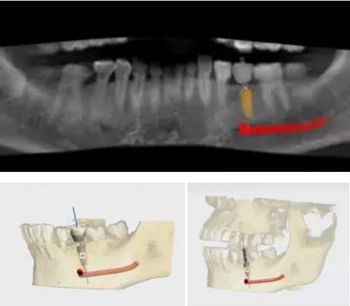

術(shù)前,導(dǎo)板設(shè)計工程師,根據(jù)CBCT以及模型數(shù)據(jù),將患者的解剖結(jié)構(gòu)、軟組織形態(tài)和修復(fù)效果數(shù)字化三維重建,在設(shè)計軟件內(nèi)進行虛擬修復(fù)體冠設(shè)計,同時與臨床醫(yī)生一起,根據(jù)#35牙槽骨高度以及寬度,結(jié)合下牙槽神經(jīng)管,設(shè)計好合適的種植位點。

根據(jù)上述植入和修復(fù)方案,立體設(shè)計Implant Guide™全程導(dǎo)板,鑒于下頜需避讓下頜神經(jīng)管,并考慮到種植體與頰舌側(cè)、近遠中側(cè)的關(guān)系,設(shè)計在該牙位植入1顆Alpha-Bio Tec ICE 4.2x 10mm的植體。

術(shù)前術(shù)后CBCT數(shù)據(jù)對比分析,植體就位準確。